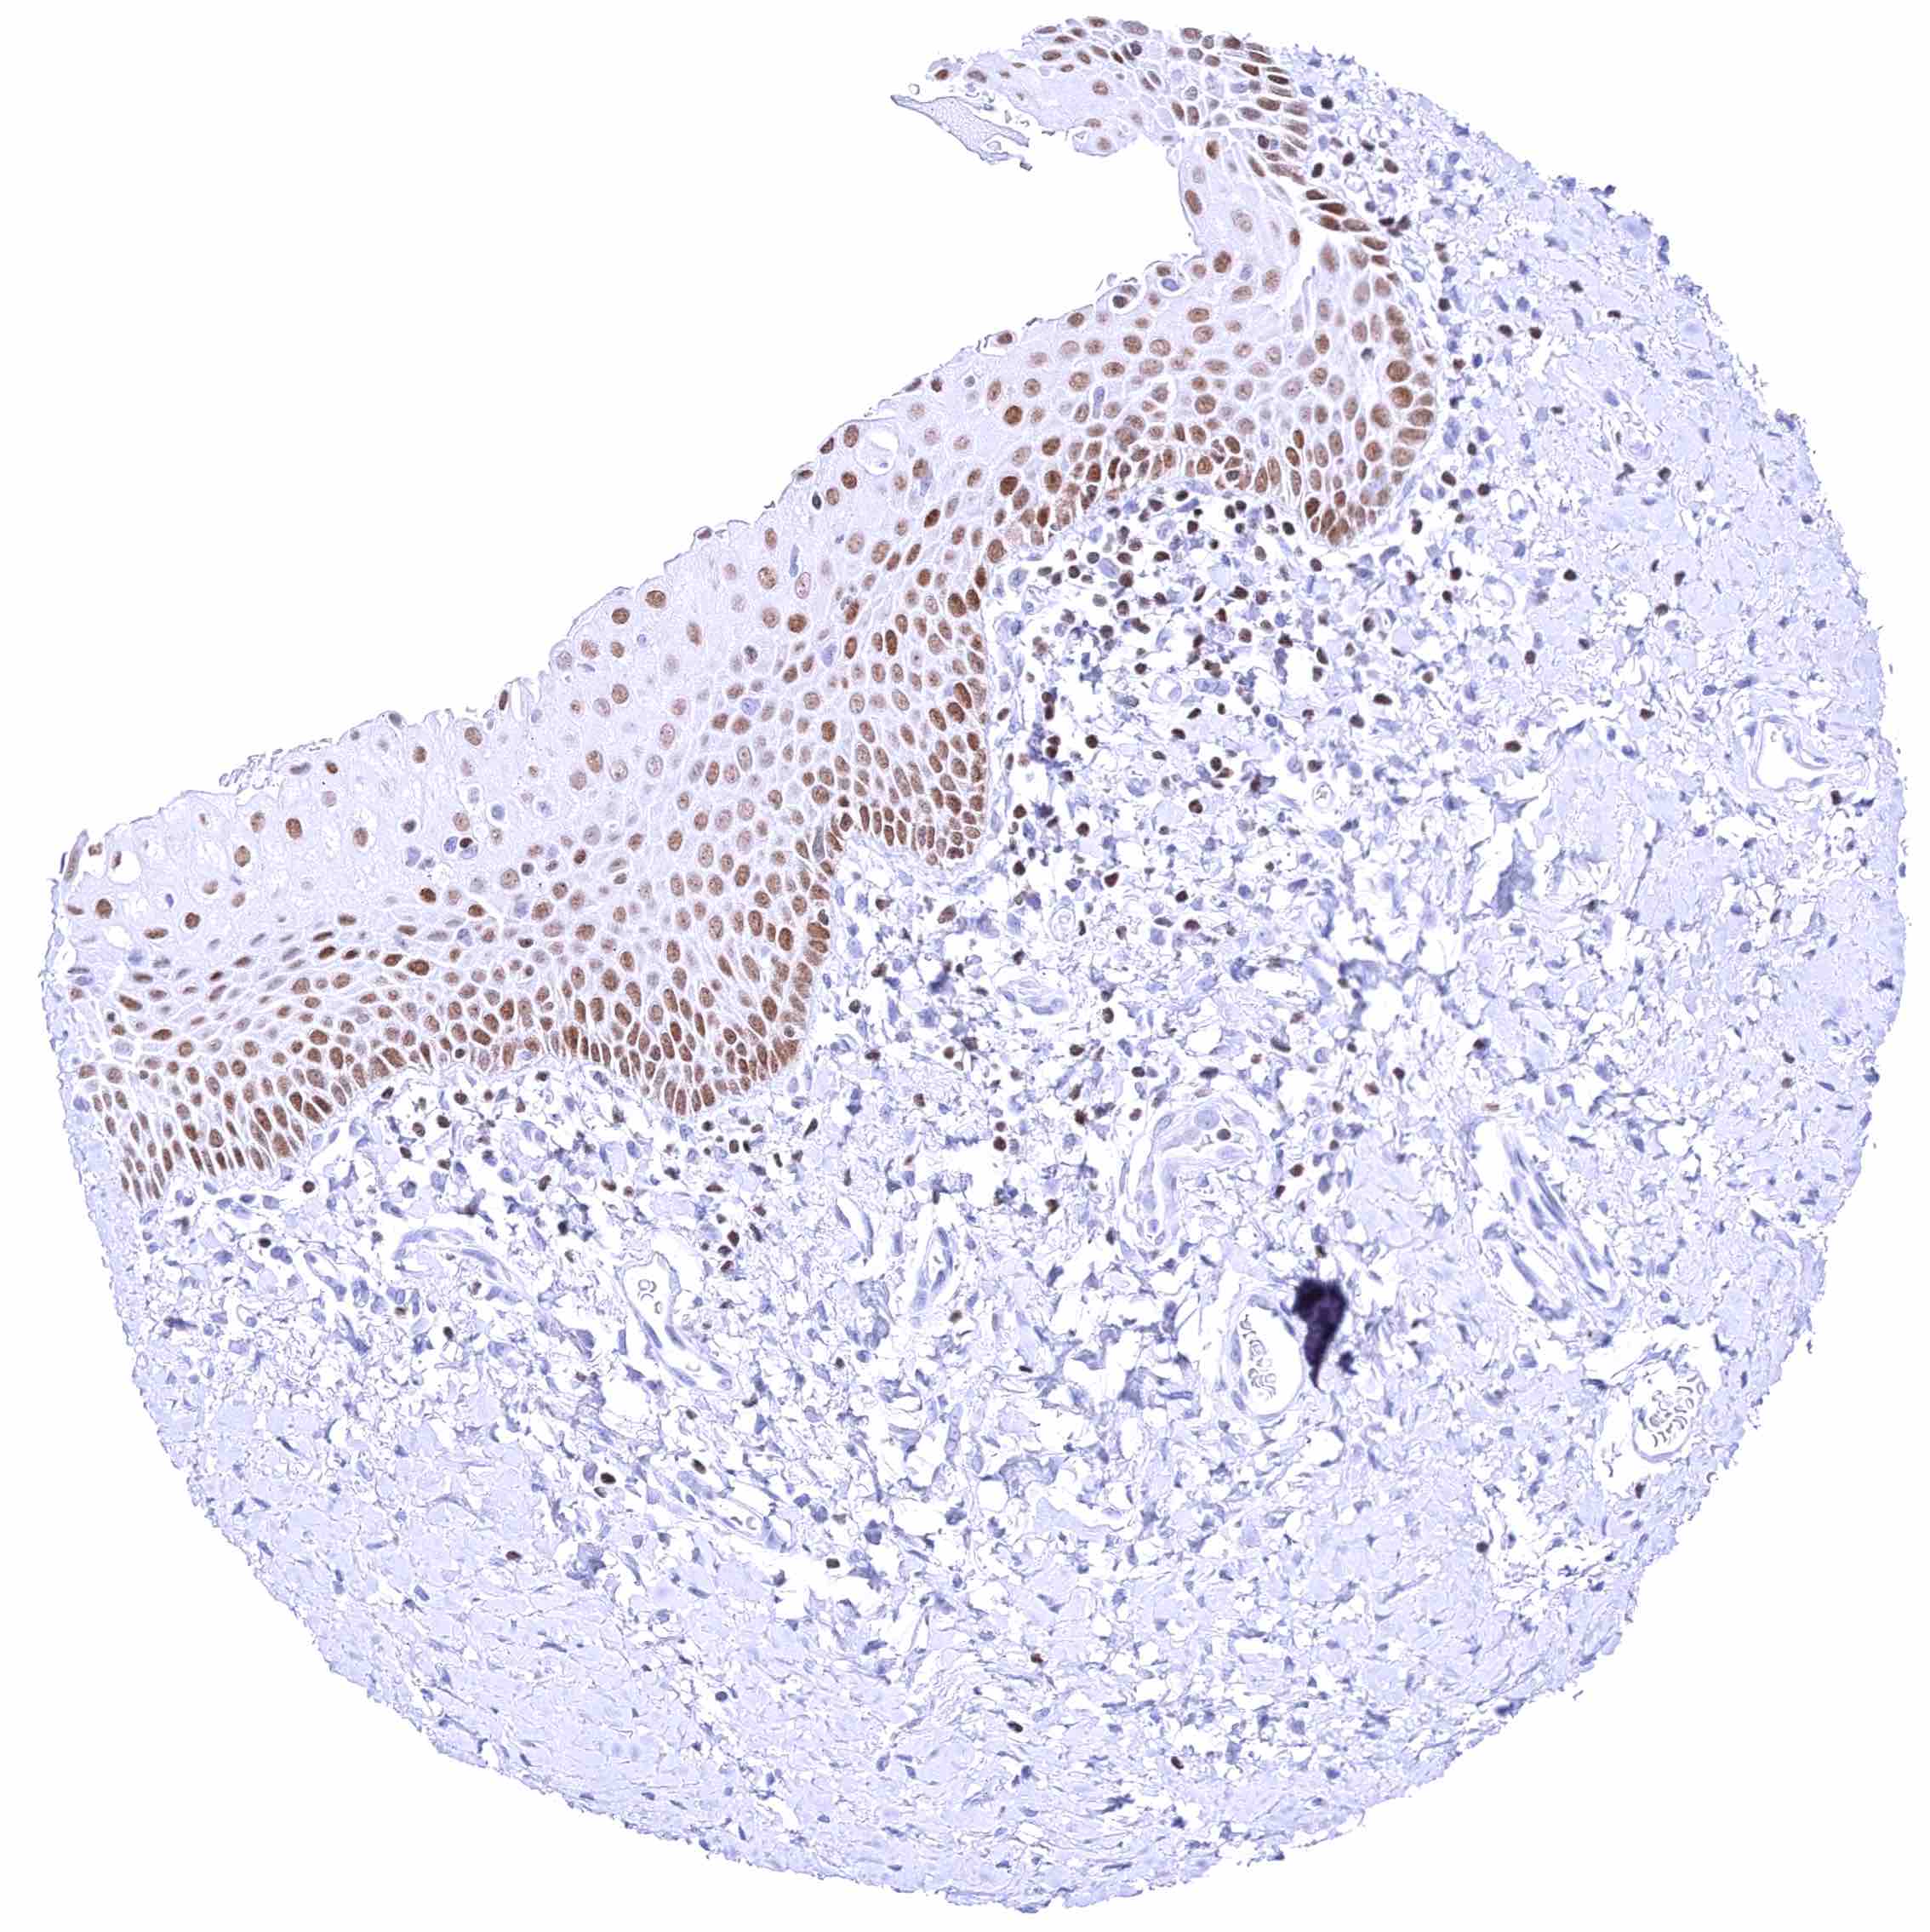

Skin – Strong nuclear GATA3 staining of squamous epithelial cells.